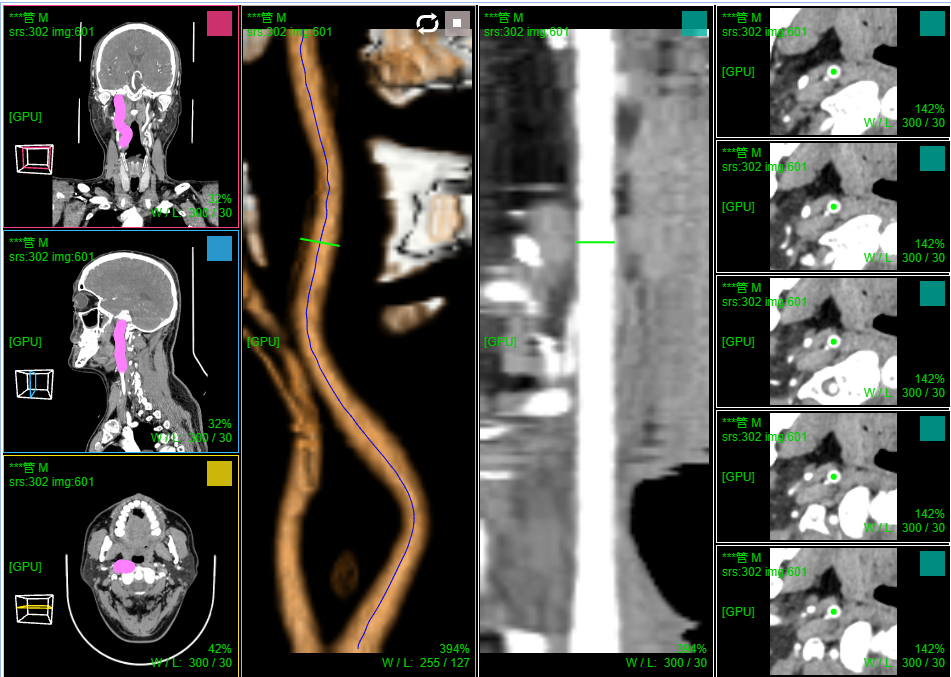

十、血管CPR曲面拉伸拉直

打开血管增强造影序列; 菜单 选择 "路径点手工标记"

在MPR切片上选取2个血管中心点,确定血管起始位置和前进方向

菜单 选择 "血管中心辅助提取"

滚轮下滚则则沿当前方向前进自动检测下一个血管中心位置和检测到的大小(图示5 圆为检测血管半径,红点为中心; 绿点为重建血管垂直切面中心)

滚轮上滚则回退并删除当前检测的血管中心点

鼠标滚轮在重建血管垂直切面右侧(图示3)上下滚动 则调整切面X轴方向以便切面和血管垂直, 在MPR上可看到该切面和血管的交线(绿线)

鼠标滚轮在重建血管垂直切面下侧(图示4)上下滚动 则调整切面Y轴方向以便切面和血管垂直, 在MPR上可看到该切面和血管的交线(绿线)

鼠标左键按下并移动则拖动改变当前检测血管中心点的位置,滚轮在检测点(红点)上滚动则调整检测的血管半径大小(仅仅确定前进步长用)

点击自动前进并检测(图示2) 则程序自动沿血管中心路径前进并检测记录中心点位置;如果检测失败则停止前进,需手工干预调整

注:自动检测前进时 还可通过包围盒裁剪设定检测截至范围

血管中心检测提取结束后,菜单 选择 "血管CPR拉直渲染"

窗口1:MPR窗口

窗口2:血管CPR拉伸; 窗口3:血管CPR拉直; 窗口4:当前血管位置(绿线)垂直重建切片和前后切片

滚轮在窗口2和窗口3上滚动可调整 当前血管位置(绿线, 图示5)

滚轮在窗口2和窗口3 右侧上下滚动 则可沿血管中心360旋转CPR

窗口2:血管CPR拉伸 支持厚切,可开启厚切